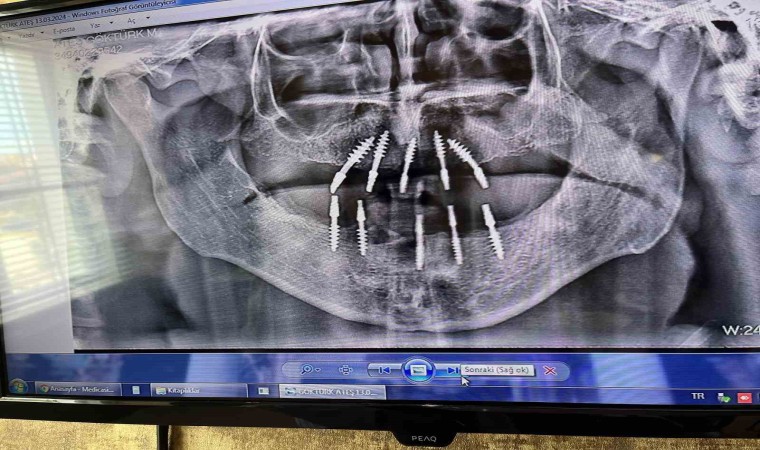

Fizyomer Terapia Estetica Denta Fizik Tedavi ve Rehabilitasyon Tıp Merkezi Diş Hekimi Mutlu Turgut, uygulanmaya başlanan ve normal implanta göre daha çabuk kullanıma hazır olan protezlere imkân sağlayan monoblok implant sistemi hakkında bilgi verdi. Monoblok implantta operasyondan 3 gün sonra protezlerin ağza yerleştirildiğini söyleyen diş hekimi Turgut, klasik implant sisteminden ayıran en önemli farkın hızlı uygulama olduğuna değindi. 150 tane Monoblok implant uyguladıklarını söyleyen Diş Hekimi Mutlu Turgut, geri dönüşlerin iyi olduğunun altını çizdi.

Monoblok implant sistemi hakkında konuşan Fizyomer Terapia Estetica Denta Fizik Tedavi ve Rehabilitasyon Tıp Merkezi Diş Hekimi Mutlu Turgut, “Monoblok implant dediğimiz sistemde klasik implanta göre avantajımız, cerrahi fazında daha az invaziv işlem yapılmasıdır. Yani punch tekniğiyle sadece diş eti üzerinde, implant yerleştirecek bölgede 2-3 milimetre çapında bir diş eti kaldırılıp aynı seansta yerleştiriliyor. Sistemin en büyük avantajı, monoblok yani tek parçadan oluştuğu için klasik konvansiyonel sistemlerdeki ölçü ara fazlarından ve bekleme süresinden bizi kurtarıyor. İşin en güzel tarafı 72 saat içerisinde yani operasyondan üç gün sonra tüm protezleri ağza yerleştirme şansı veriyor. Hastamız kliniğimize başvurduğunda, bölgesel olarak değişmekle birlikte 1-1 buçuk saatlik bir operasyondan sonra tüm işlem bitmiş bir oluyor. Hastamız üç gün içerisinde protezlerine kavuşabiliyor. Sistemin en büyük avantajı süre kısaltma” dedi.

“Konvansiyonel sistemlerde, implant yerleştirme operasyonundan sonra hastanın kemik yapısına ve genel sağlık durumuna bağlı olarak üç ile dört ay beklenmesi gerekiyordu. Kaynama süresi için bu yeni mono sistemde bekleme süresi 72 saate kadar düşüyor. En büyük avantajımız bu. Şu anda yaklaşık 150 adet uyguladık herhangi bir komplikasyonla karşılaşmadık. Tabii genel implant komplikasyonlarının hepsi burada da geçerli. Hastanın işlemden sonrası ağız hijyeni, sigara kullanımı, genel sağlık durumu, diyabet vb.hastalıklar yani kemik yapınızı ve iyileşme prosedürünü etkileyebilecek her şey bu implant sisteminde de etkili. Fakat burada immediat yükleme olduğu için implantın osentegrasyon şansı daha fazla. Çünkü ağza yerleştirildikten sonra ne kadar kısa sürede fonksiyonu verirseniz implantın kemik ile kaynaması o kadar güzel ve kolay oluyor.”